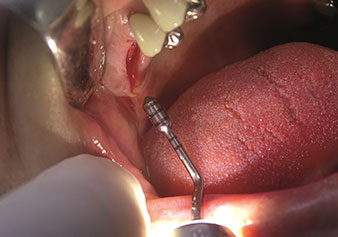

Indikation Interner Sinuslift

W&H bietet auch die perfekte Lösung für den internen Sinuslift an Nach der Kieferhöhlenpräparation mit dem

entsprechenden Instrumentarium (Abb. 3) erfolgt mit dem neuen Instrument Z35P (Abb. 4) die hydrodynamische Abhebung der Membran. Mit dem gleichen Instrumentenset kann auch die Implantatbett-Aufbereitung piezochirurgisch in aufsteigenden Durchmessern erfolgen (Abbildung drei und vier mit freundlicher Genehmigung von Dr. Mario Kirste, Frankfurt/Oder).

Implantatbettaufbereitung mit Instrument I4P

Abb. 3: Implantatbettaufbereitung mit Instrument I4P. Foto: © Dr. Mario Kirste (Frankfurt / Oder)